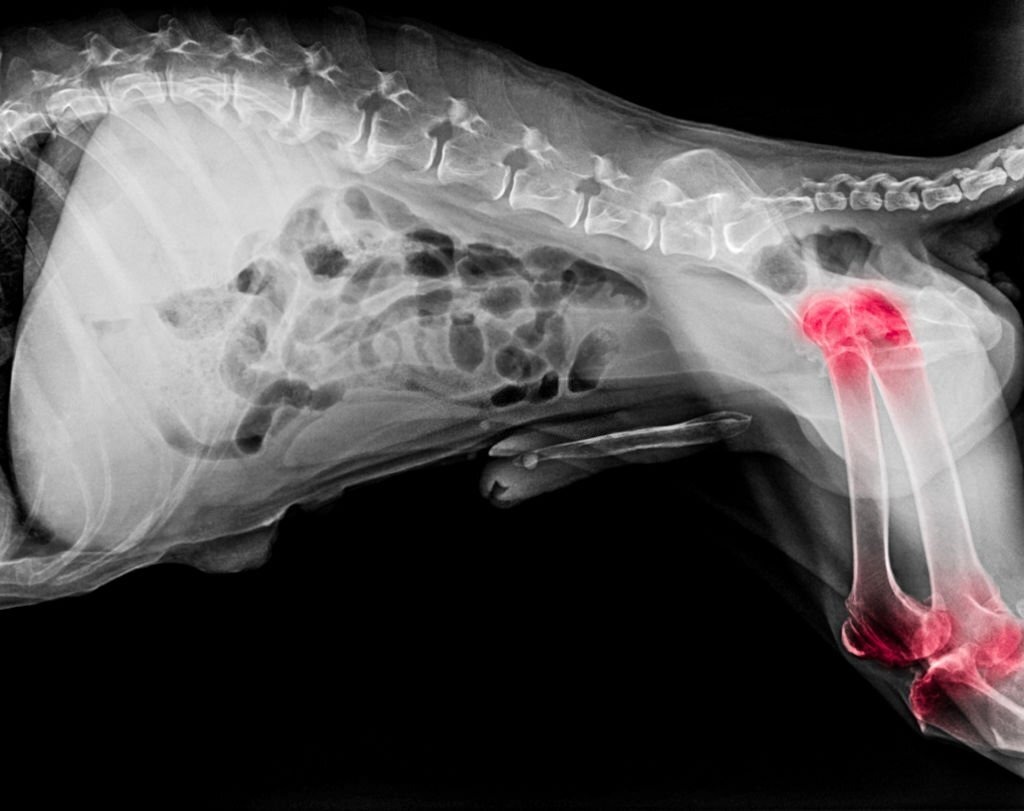

Tiếp theo, bác sĩ thú y sẽ sử dụng các phương pháp xét nghiệm hình ảnh như X-quang hoặc siêu âm để đánh giá tình trạng khớp của mèo. X-quang giúp phát hiện những thay đổi trong cấu trúc xương và khớp, chẳng hạn như sự hẹp của khe khớp, mất mát mô mềm hoặc hình thành gai xương. Siêu âm có thể cung cấp cái nhìn sâu hơn về các mô mềm quanh khớp, từ đó hỗ trợ việc xác định mức độ nghiêm trọng của bệnh.